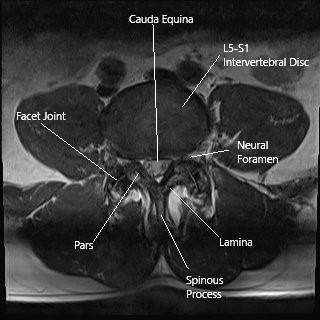

Modern imaging techniques have revolutionized the ability to pinpoint both obvious and hidden issues. For patients with suspected lower limb claudication, MRI stands as the gold standard for exploring spinal degeneration, including conditions such as lumbar facet joint synovial cysts. These cysts form due to degeneration of the facet joint and may impinge on the spinal canal, triggering neurogenic pain.

CT angiography, on the other hand, provides a clear picture of the vascular system. Its high-resolution capabilities allow clinicians to identify precise locations and the severity of arterial stenoses, such as those affecting the common and superficial femoral arteries. In combining these imaging modalities, healthcare providers are better equipped to figure a path through the multiple layers of pathology.